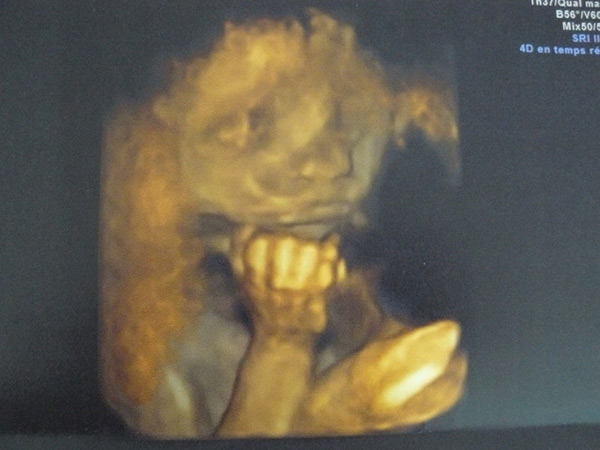

Depuis quelques mois, quelque chose grandissait et par un froid matin de décembre, notre petite Lisa est née.